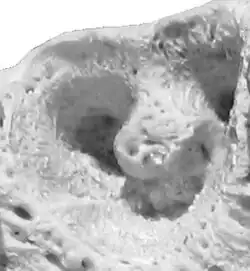

Alvéolo dentário

Na odontologia, um alvéolo dentário é a cavidade do osso da maxila e mandíbula onde se alojam os dentes.[1][2] O alvéolo existe em função dos dentes; na perda destes, o alvéolo deixa de existir.[3] Sua função principal é dar suporte aos dentes, para que possamos mastigar os alimentos. São cavidades nos maxilares nas quais as raízes dos dentes são mantidas no processo alveolar com o ligamento periodontal. O termo leigo para alvéolos dentais é cavidades dentárias. A articulação que conecta as raízes dos dentes e o alvéolo é chamada de gonfose (plural gomfoses). O osso alveolar é o osso que circunda as raízes dos dentes, formando cavidades ósseas.